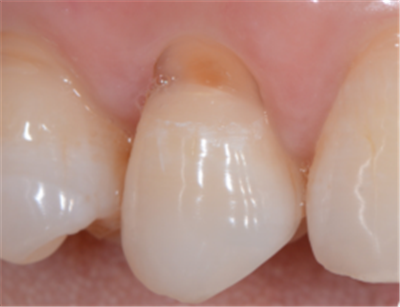

2.牙齿缺损:

楔状缺损

牙齿隐裂或折裂

3.旧的补牙材料脱落: